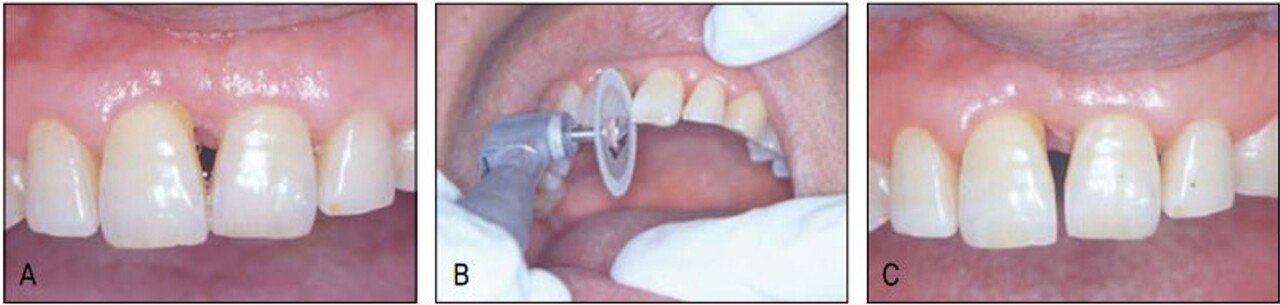

아직도 많은 이들이 교정은 심미목적으로만 치료받는 것으로 잘못 알고 있고, 이에 대한 계몽이 필요하다는 것을 본 증례가 여실히 보여주었다. 과개교합으로 인해 순측부착이 불가하여 설측으로 장치를 부착하였더니 보이지 않는 장치라 환자가 매우 좋아하였다. 한 개의 와이어를 사용하여 간단히 하악교정을 한 후 환자에게 다시 상악 교정을 권유하였더니 환자는 흔쾌하게 상악도 교정을 하겠다고 하였다. 하악에서처럼 심미적 교정장치로 치료 받을 수 있을 것으로 기대했기 때문이었다. 그러나 전치부 과개교합으로 상악설측면에서의 장치 부착이 불가하여 환자에게 투명교정장치를 설명하였고 이 역시 심미적 장치이어서 환자가 수락하고 투명교정장치로 간단하게 공간클로져 교정을 시행하였다.

가철식 장치이어서 다소의 경사이동이 발생하였고 치주질 환으로 우측의 중절치가 더 정출하여 비심미적인 절단연이었으나 스트리핑 그리고 re-shaping 등을 이용하여 심미적인 절단연을 만들어주었다. 교정을 주저하였던 환자는 설측 및 투명장 치 등 심미적 장치로 인해 교정치료 내내 크게 만족해 하였다(그림 23-7~10).